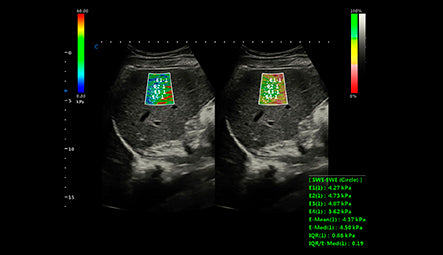

Elastografía de Onda Cortante y Rigidez Tisular en Tiempo Real

Una de las características más destacadas del SonoMax 9 es su capacidad de realizar elastografía de onda cortante, que permite una evaluación cuantitativa de la rigidez tisular. Esta tecnología es crucial en áreas como la hepatología y la oncología, ya que proporciona datos precisos sobre la elasticidad de los tejidos. Al medir la velocidad de las ondas generadas por el tejido pulsado, los médicos pueden obtener una imagen detallada de la rigidez tisular, facilitando diagnósticos más informados y decisiones clínicas más acertadas. Esto es especialmente útil en el seguimiento de enfermedades hepáticas crónicas y en la evaluación de masas tumorales.